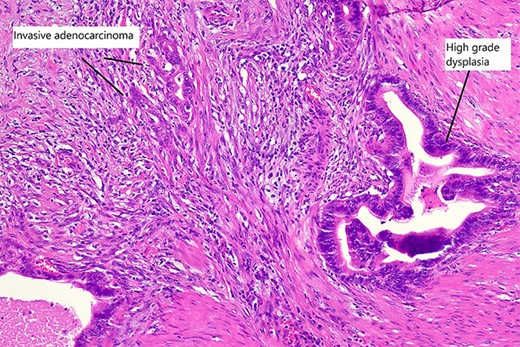

Final histopathological assessment of the resected specimen reported a common bile duct adenocarcinoma (cholangiocarcinoma) measuring 37 mm in greatest dimension with extensive perineural, periductal, perinodal and peripancreatic soft tissue involvement. Metastatic carcinoma was found in 3/17 lymph nodes resected. The cholangiocarcinoma was staged as pT2N1M0. The gallbladder was found to have extensive high-grade biliary intraepithelial neoplasia with a primary gallbladder adenocarcinoma measuring 18 mm in greatest dimension entirely separate from the cholangiocarcinoma (Fig. 5). The patient recovered well from the procedure and was discharged home from hospital on post-operative Day 15. She has proceeded to have further treatment with adjuvant chemotherapy.

High magnification slide showing high-grade dysplasia and invasive adenocarcinoma of the gallbladder after haematoxylin and eosin staining.